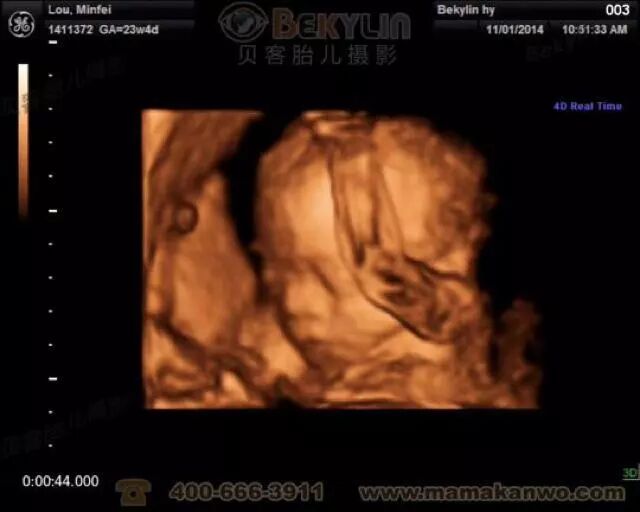

大排畸通常在22-26周进行,通过B超查宝宝的五官 、四肢以及内部各个器官有无异常。

如果想给宝宝留下在妈妈肚子里的视频,可以在这个阶段做四维彩超。可以比较清楚的看到小宝宝长什么样子。